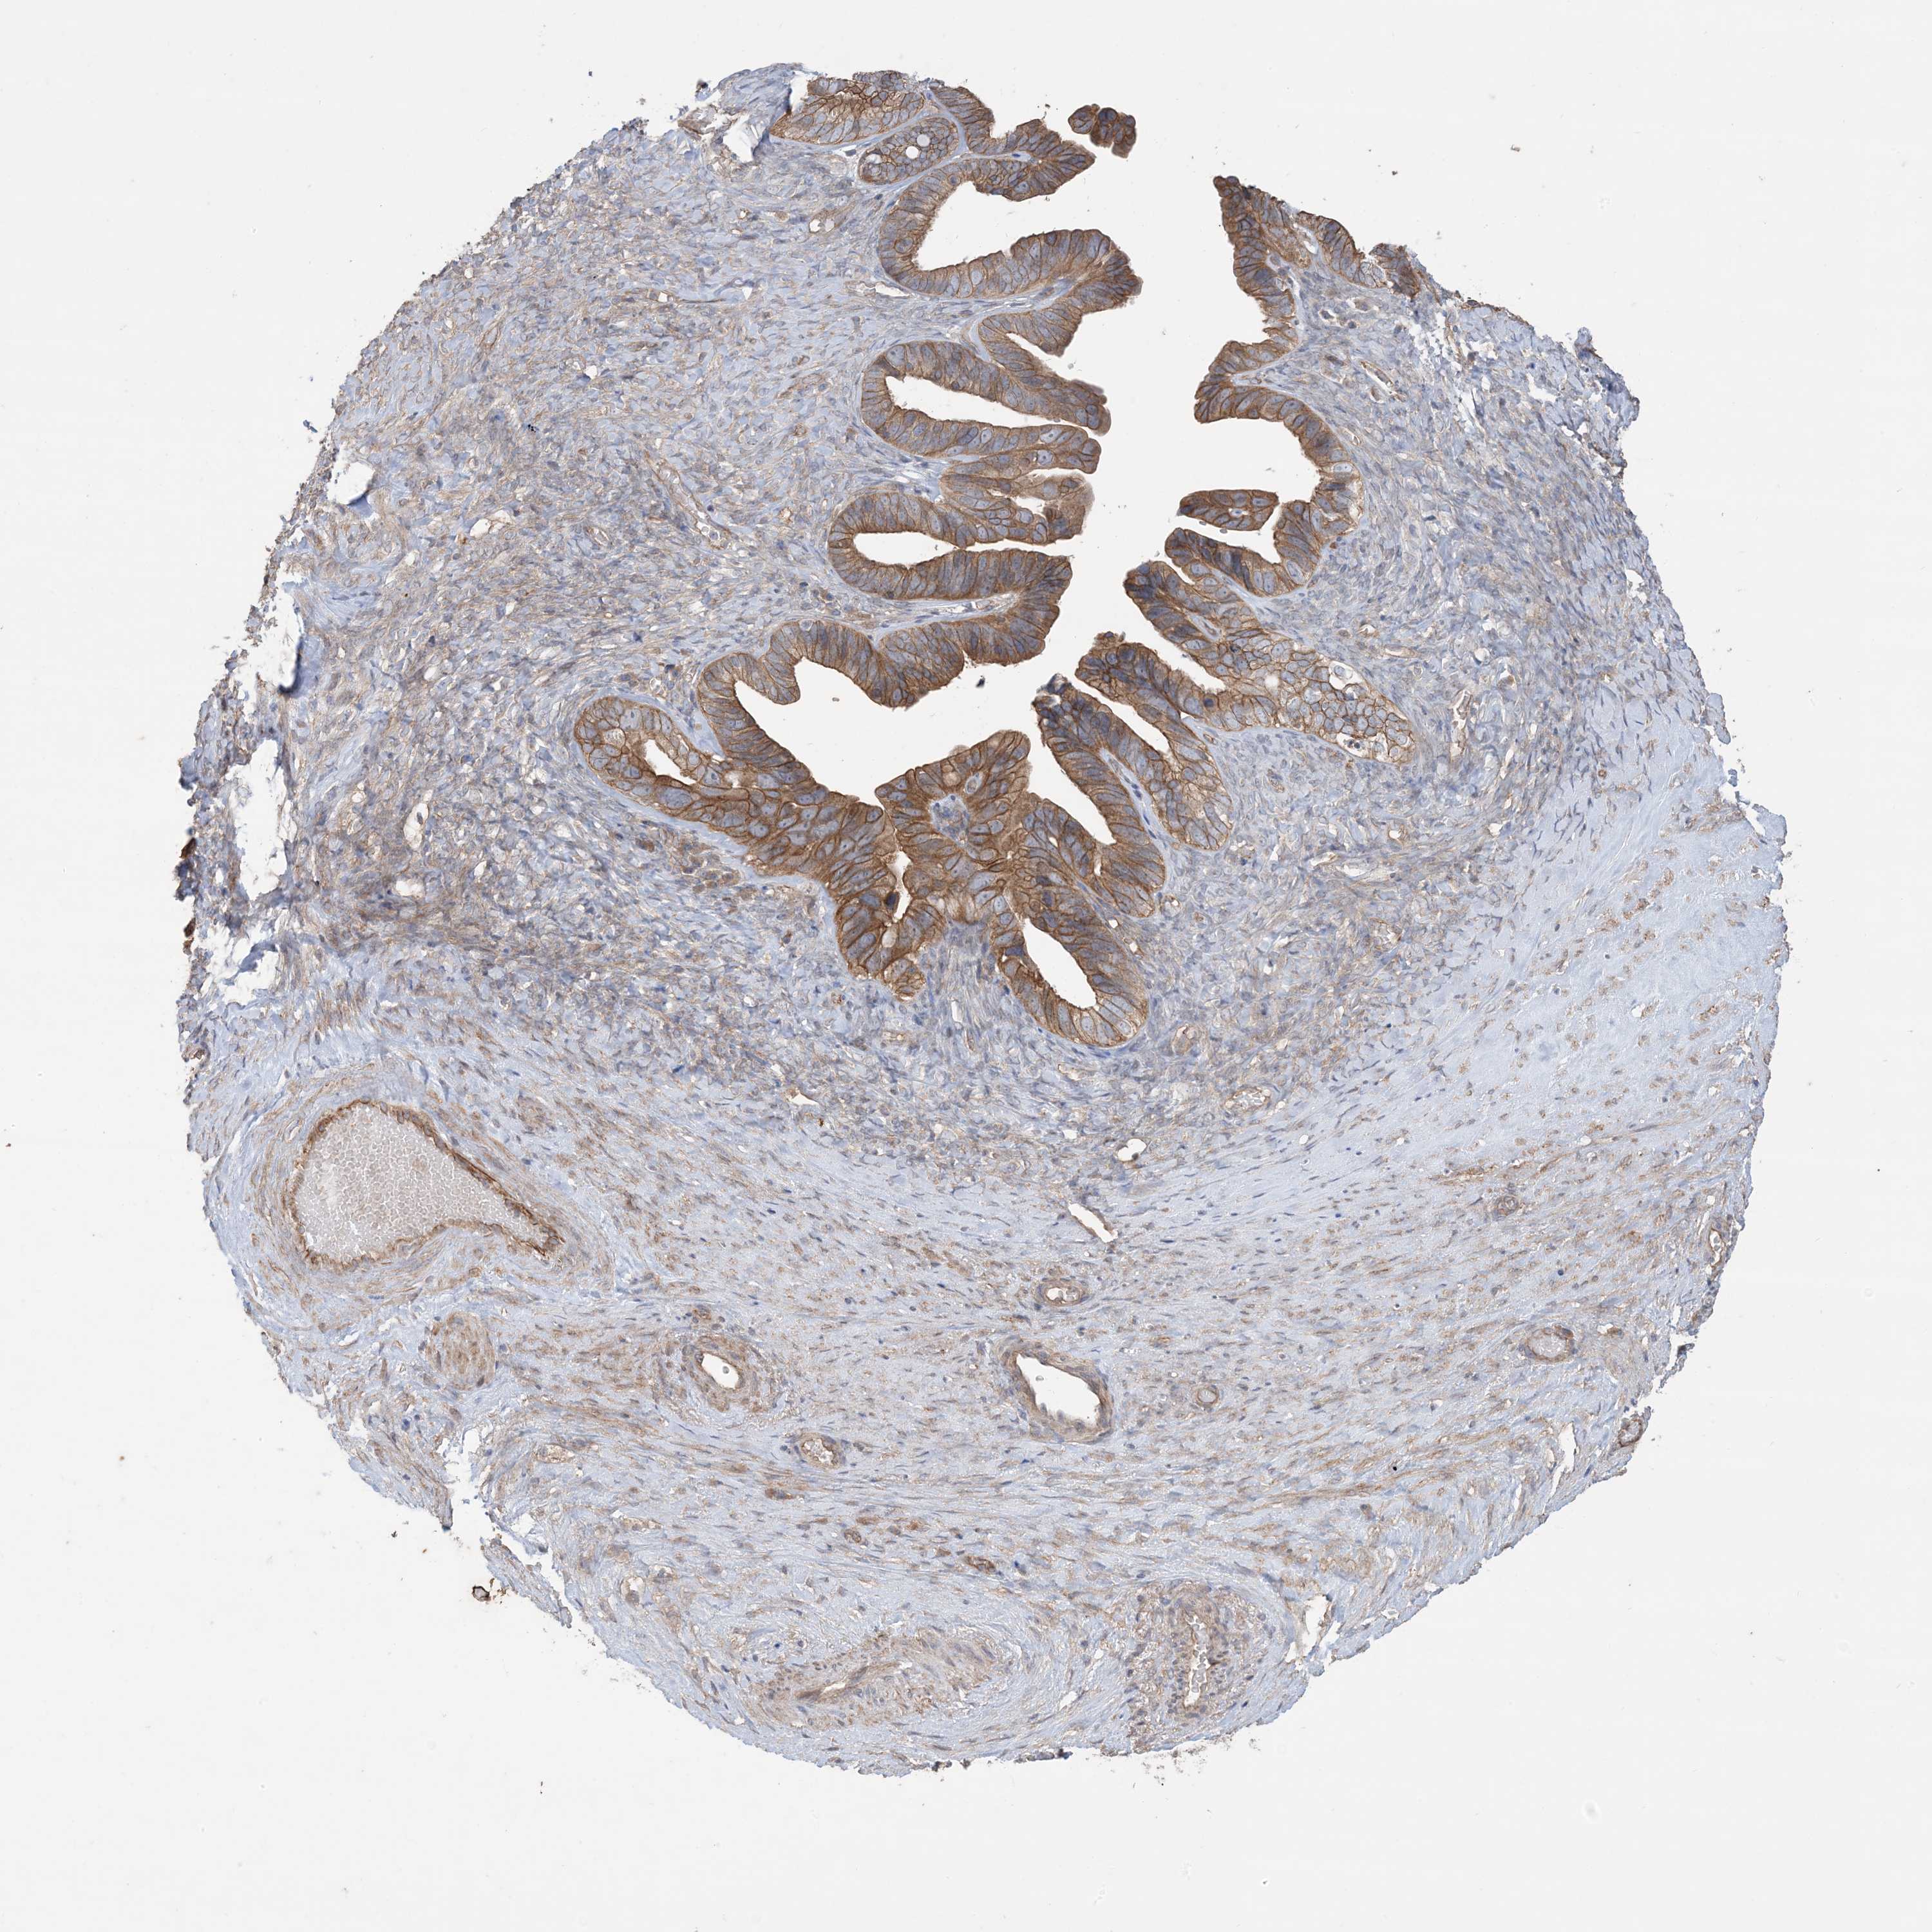

OVARIAN CANCER - Protein expressioni

A mouse-over function shows sample information and annotation data. Click on an image to view it in a full screen mode. Samples can be filtered based on level of antibody staining by selecting one or several of the following categories: high, medium, low and not detected. The assay and annotation is described here.

Note that samples used for immunohistochemistry by the Human Protein Atlas do not correspond to samples in the TCGA dataset.

Antibody stainingi

Antibody staining in the annotated cell types in the current human tissue is reported as not detected, low, medium, or high, based on conventional immunohistochemistry profiling in selected tissues. This score is based on the combination of the staining intensity and fraction of stained cells.

Each image is clickable and will lead to virtual microscopy that enables deeper exploration of all samples and also displays staining intensity scores, fraction scores and subcellular localization as well as patient and tissue information for each sample.

Antibody HPA036290

Staining

High

Medium

Low

Not detected

Intensity

Strong

Moderate

Weak

Negative

Quantity

>75%

75%-25%

<25%

None

Location

Nuclear

Cytoplasmic/membranous

Cytoplasmic/membranous,nuclear

Cystadenocarcinoma, serous, NOS

Carcinoma, endometroid

Cystadenocarcinoma, mucinous, NOS

Carcinoma, NOS